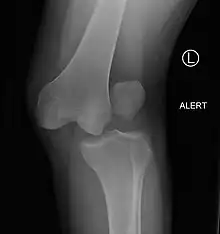

| Plain lateral X-ray of the left knee showing a posterior knee dislocation[1] | |

Plain X-rays, CT scan, ultrasonography, or MRI may help with the diagnosis.[2][11] Findings on X-ray that may be useful among those who have already reduced include a variable joint space, subluxation of the joint, or a Segond fracture.[5]

They may be divided into five types: anterior, posterior, lateral, medial, and rotatory.[4] This classification is based on the movement of the tibia with respect to the femur.[11] Anterior dislocations, followed by posterior, are the most common.[2] They may also be classified on the basis of which ligaments are injured.[2]